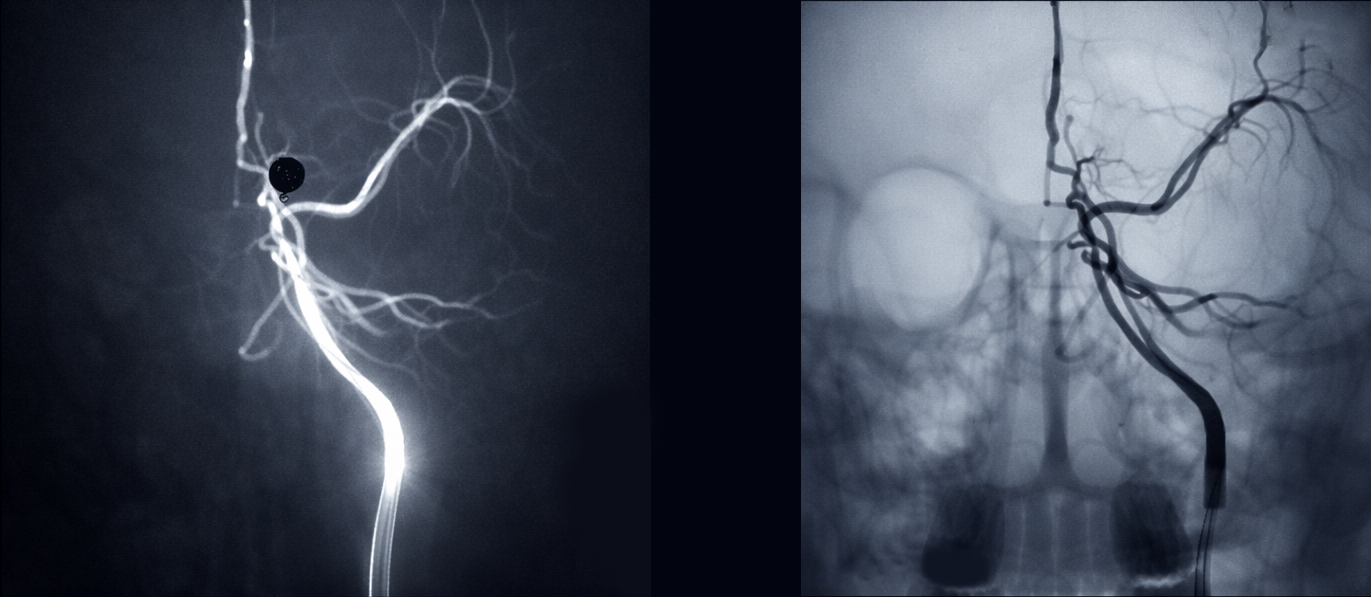

• Switch between simulated and DSA imaging modes

• Visualize contrast flow during injection

• Replicate real angiographic imaging workflows